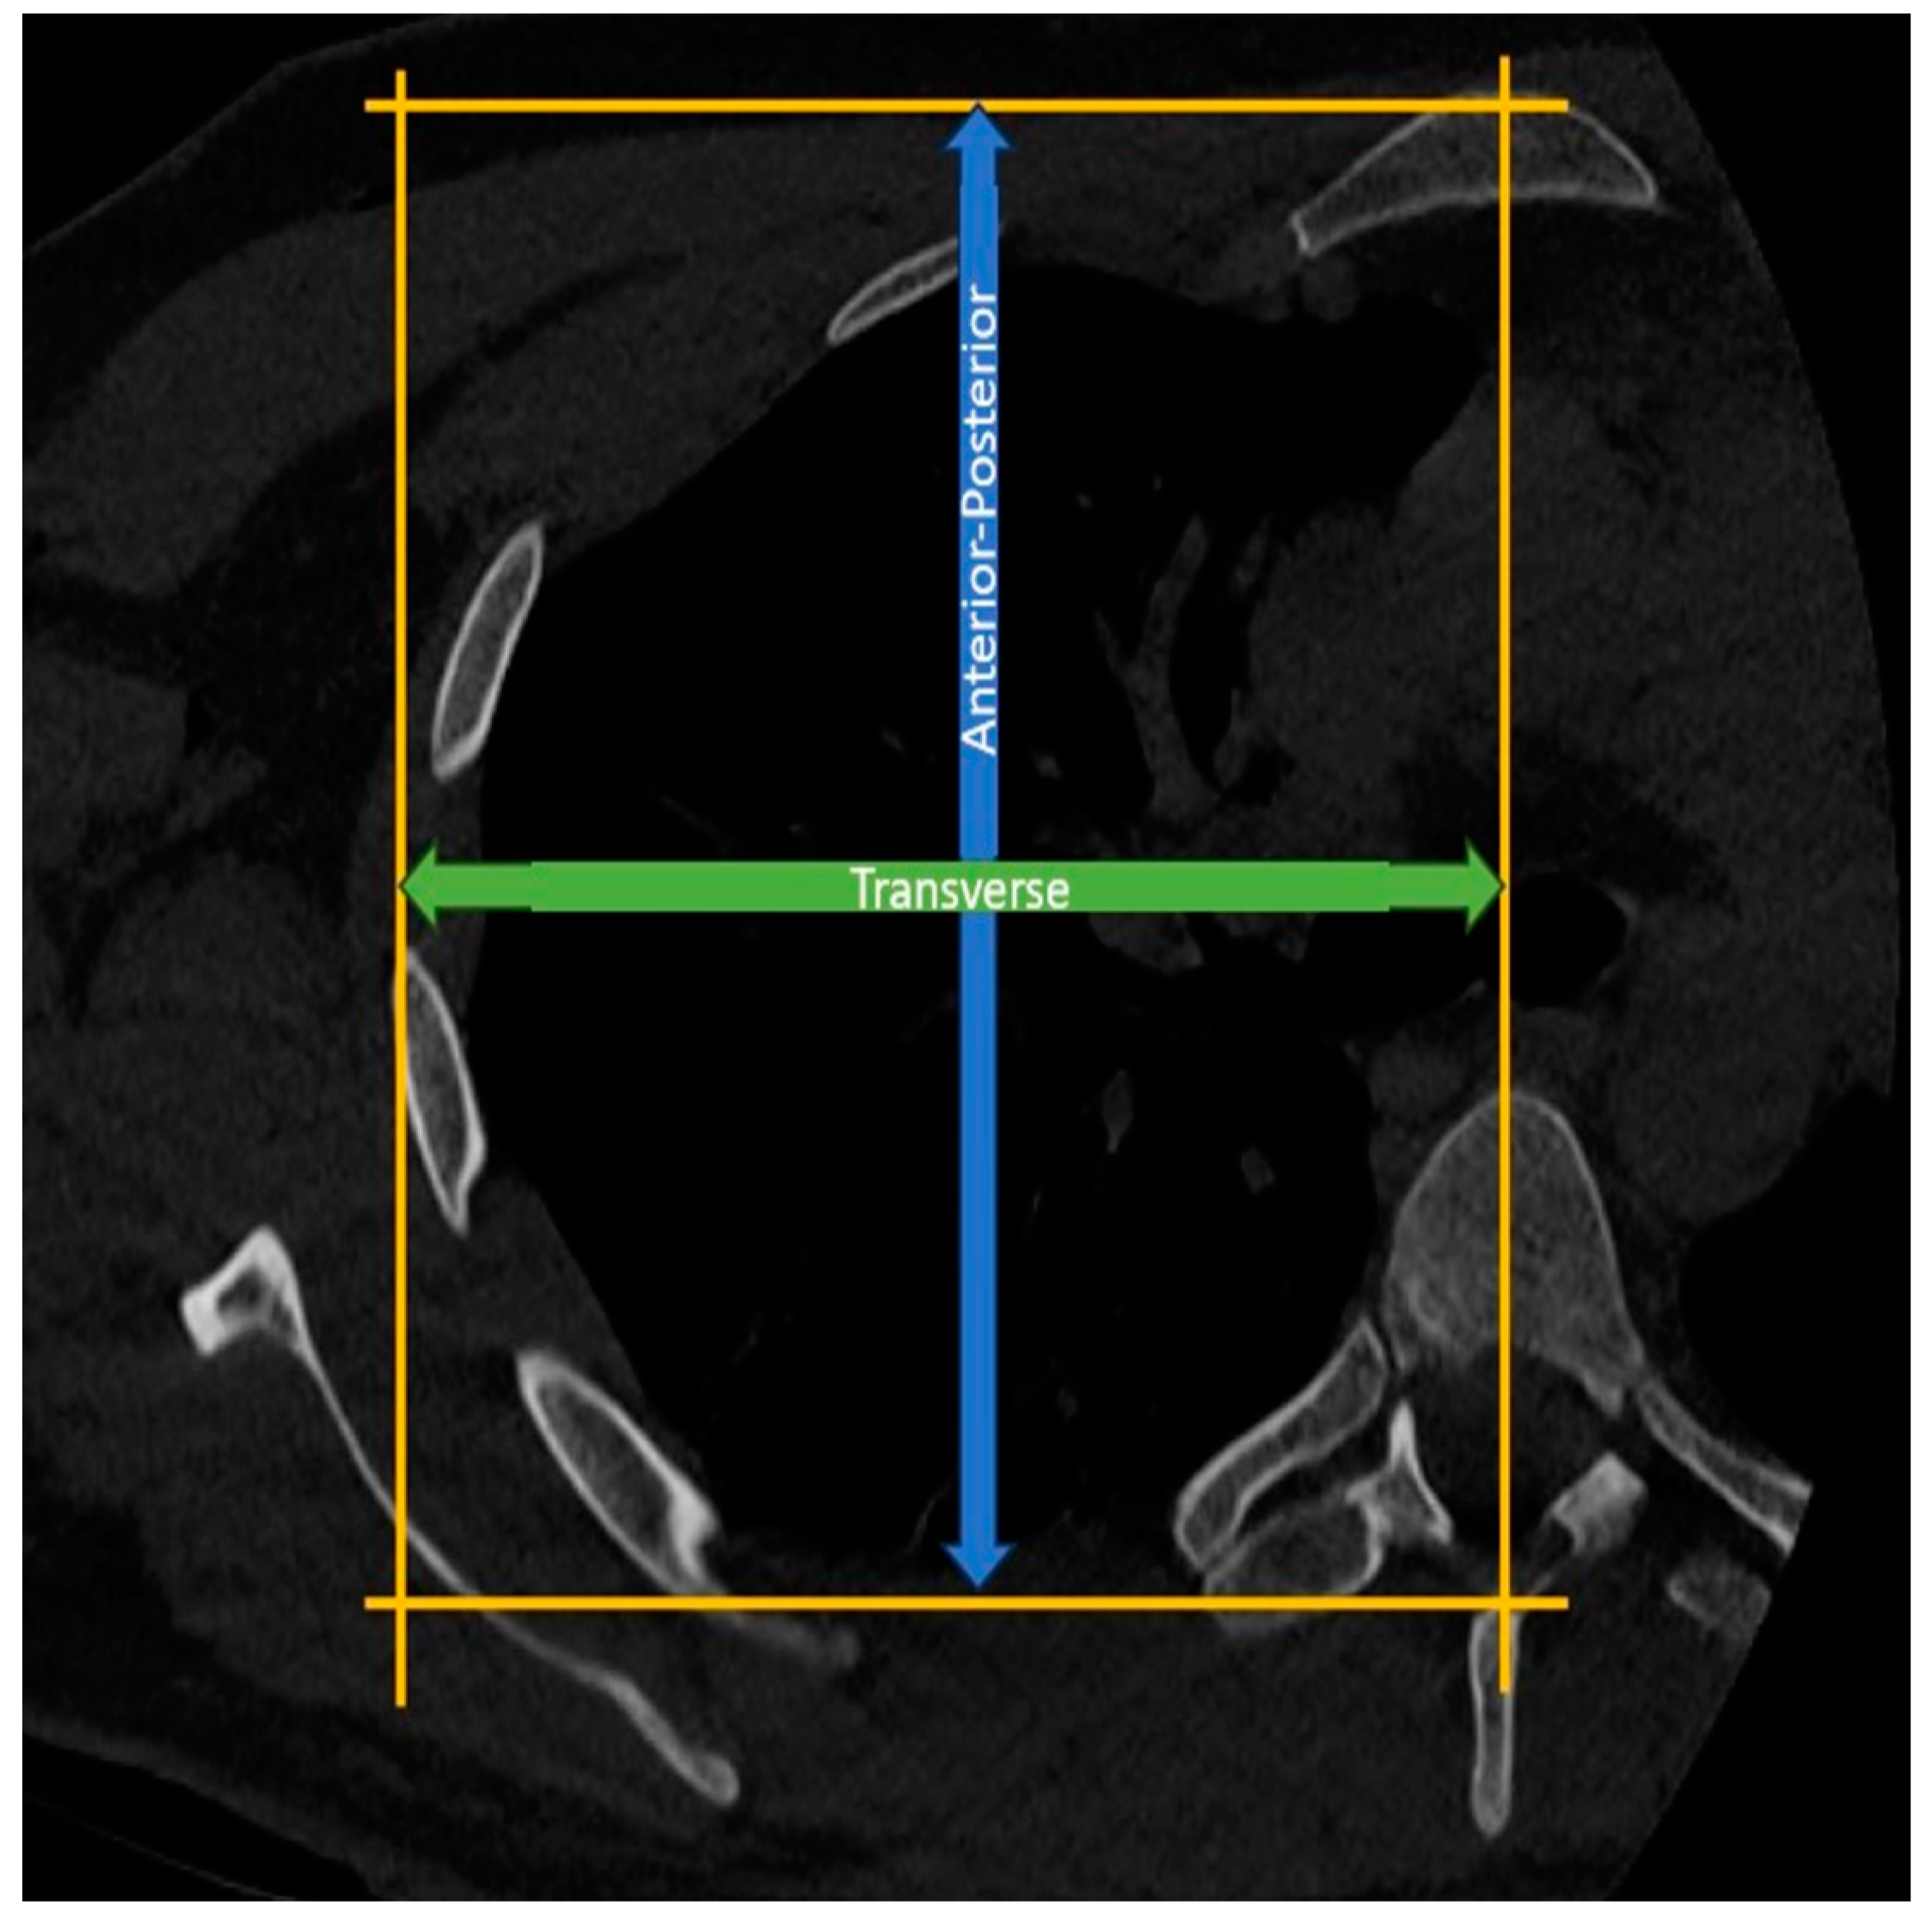

Measurement of Thoracic Anterior-Posterior Diameter: In the axial CT sections at the T4-5 level, the length between a line drawn parallel to the sternum from the anterior surface of the sternum and another line drawn parallel to this line from the apex of the spinous process of the corresponding vertebra is assessed as the thoracic anterior-posterior diameter (Figure 4).

Measurement of Hemithoracic Transverse Diameter: In the axial CT sections at the T4-5 level, a vertical line is drawn from the midline of the vertebra, connecting a line drawn parallel to the sternum from the anterior surface of the sternum and another line drawn parallel to this line from the lateralmost part of the corresponding rib. The distance between these lines is then assessed as the thoracic transverse radius (Figure 4).

Figure 4. Measurement of anterior-posterior thoracic and transverse hemithoracic diameter.